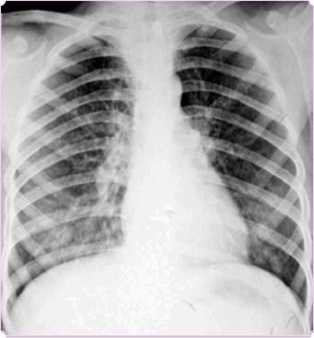

圖中可見右上葉“斑點花”,根據(jù)公式診斷為小葉性肺炎